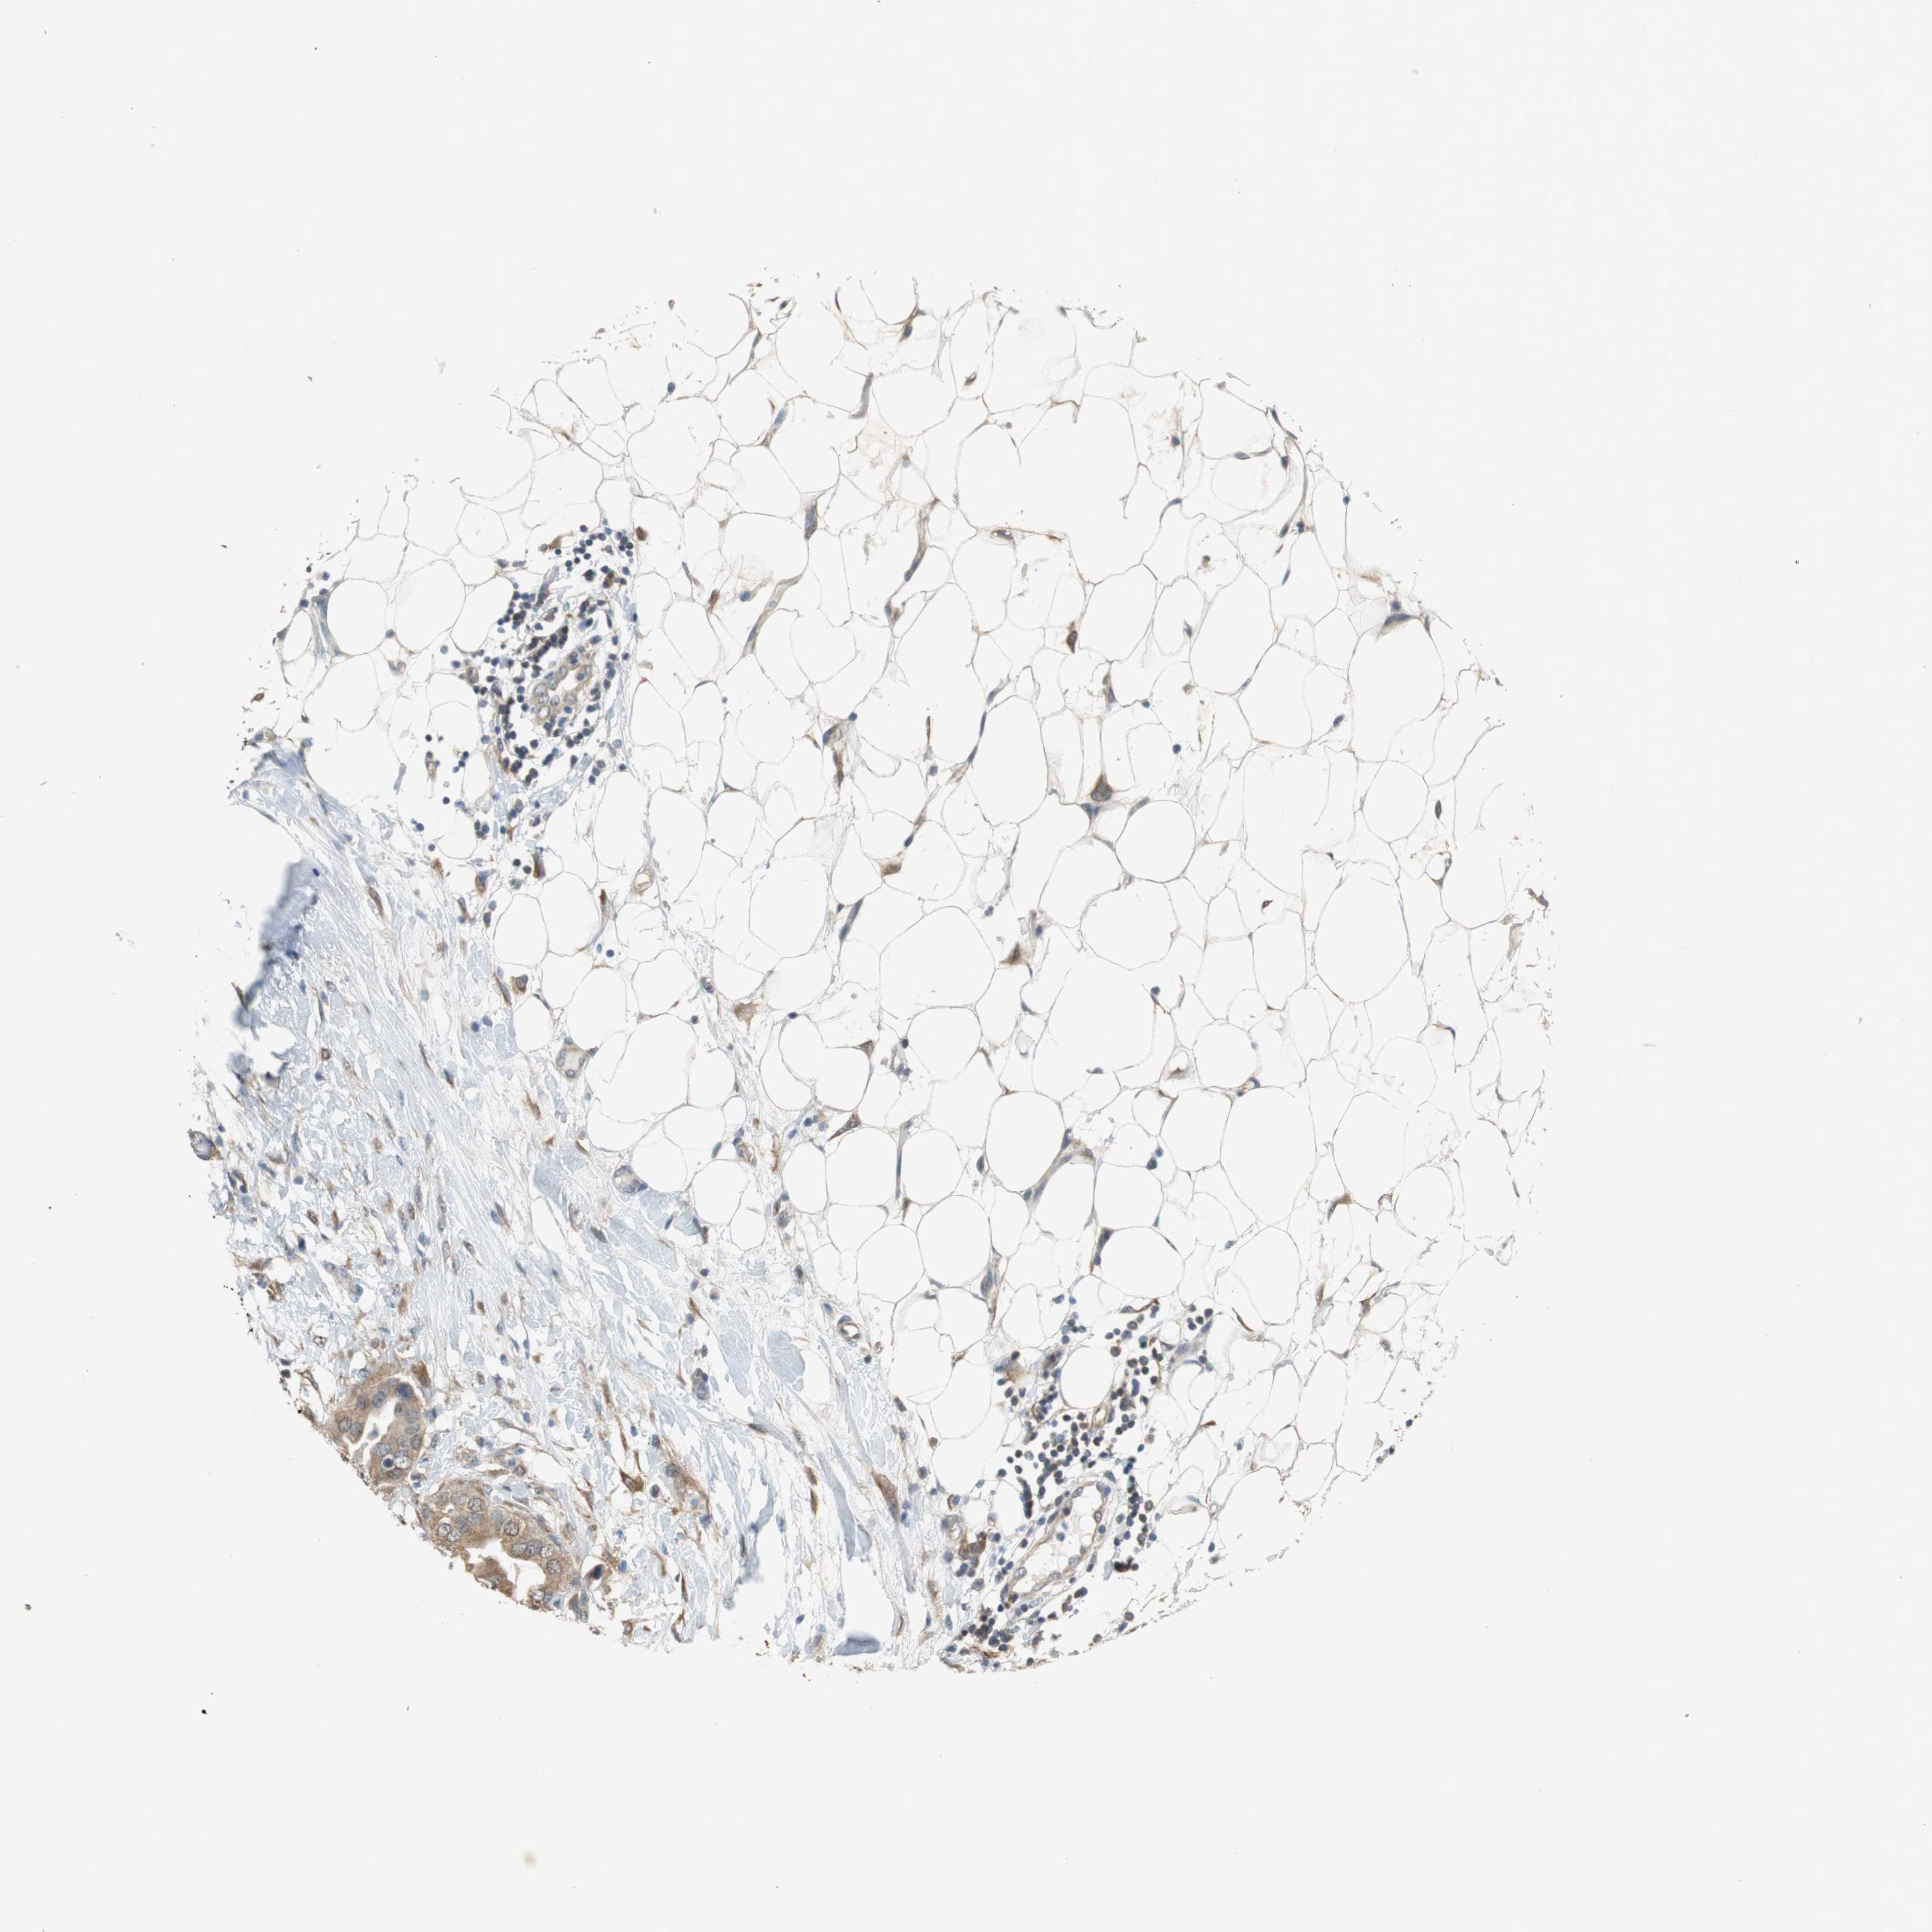

BRCA TCGA BRCA VALIDATION PROTEIN EXPRESSION